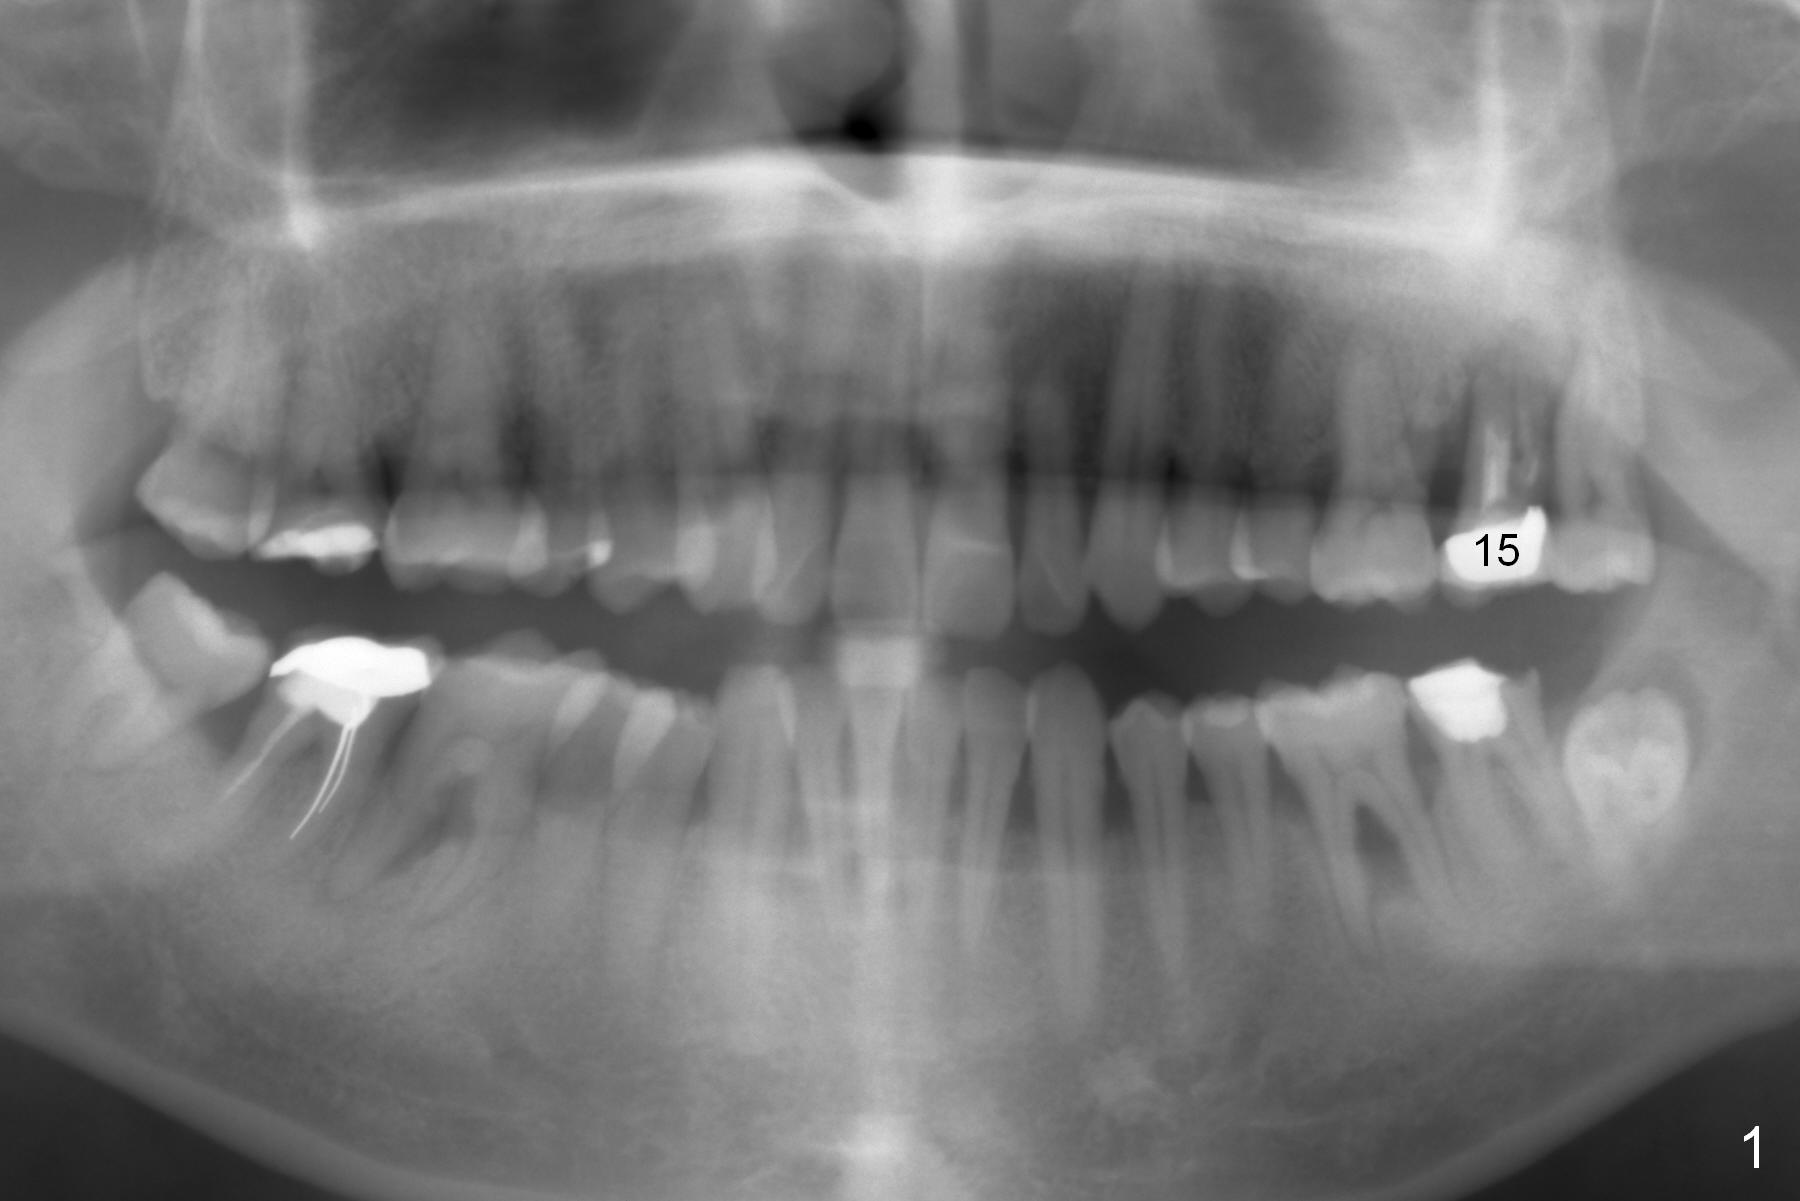

A 47-year-old man (LW) agrees to have the tooth #15 (Fig.1) extracted for implant after 4-year delay (Fig.2).  A 20 mm long implant will have at least 6 mm native bone for stabilization (Fig.3).  Bone density seems to be high.  Use Bicon drill and reamers until 3.5 mm, followed by 5x20 mm Tatum tapered tap and PA.